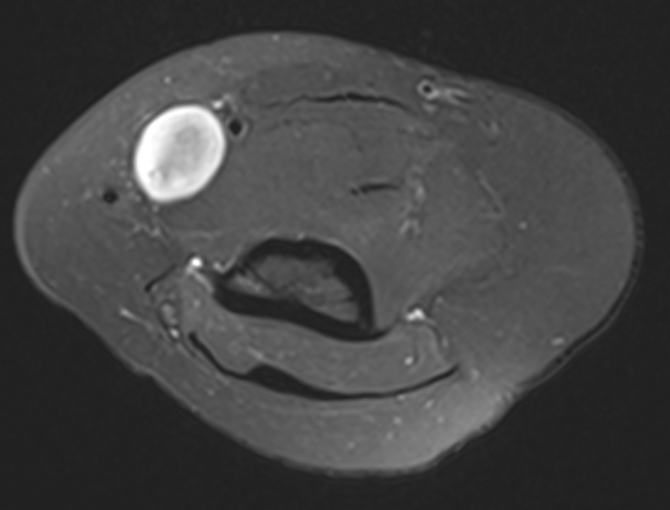

MRI

Target sign

- hypointense centrally

- hyperintense peripherally

Neurofibroma common peroneal nerve